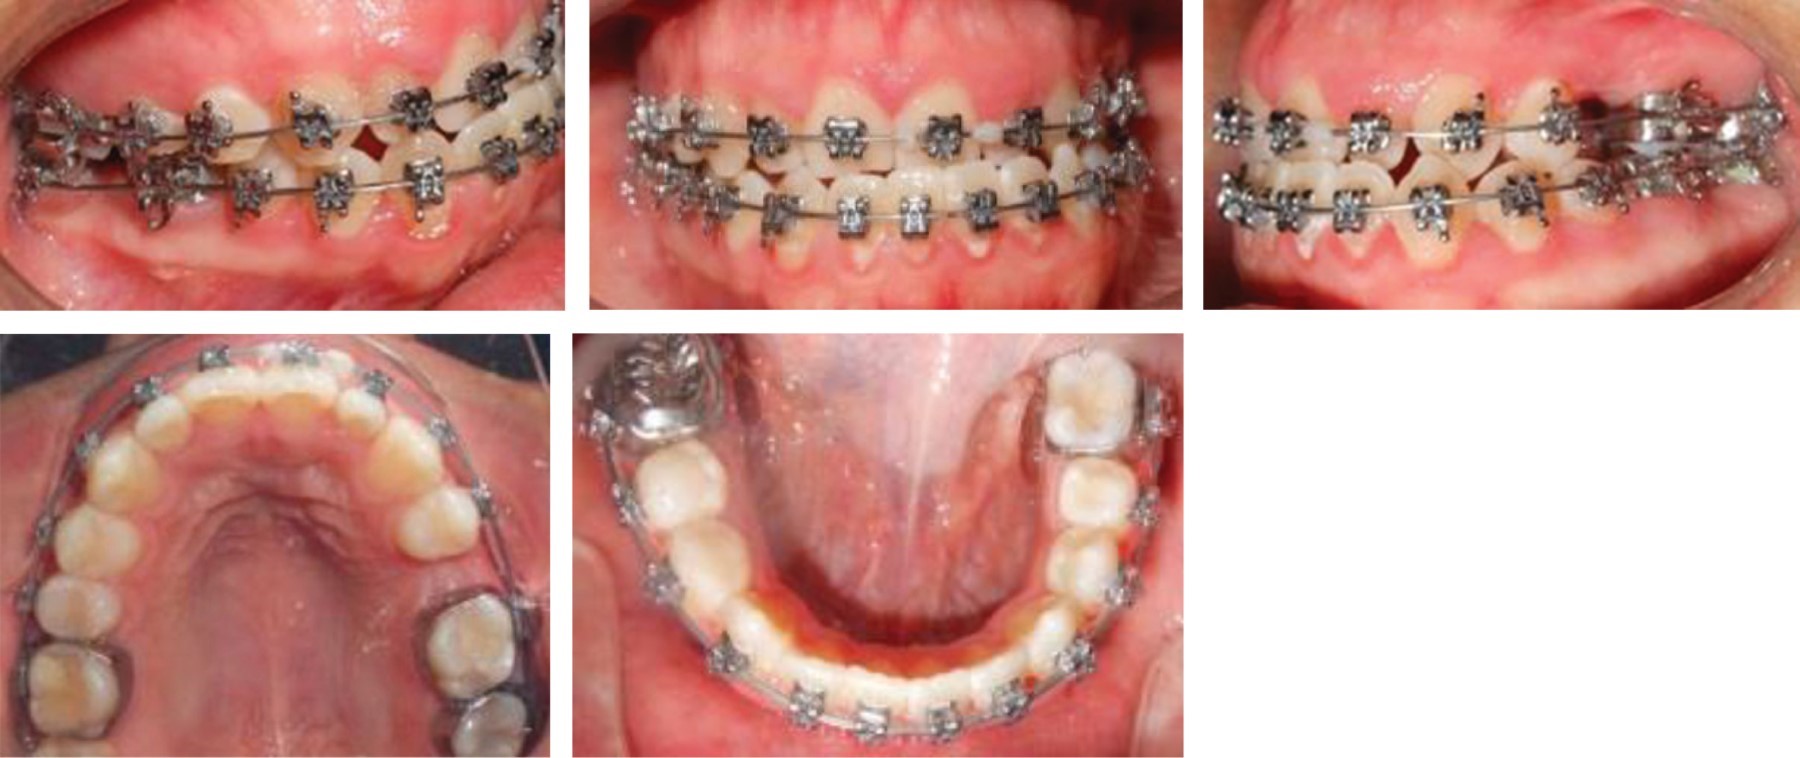

After the extraction of the third molars, we proceeded to the placement of fixed appliance Roth self-ligating slot 0.022" to begin phase I, starting with NiTi 0.014" archwires in both arches to begin with the alignment and leveling (Figure 6).

The treatment continued in the first phase, aligning and leveling, using 0.016" NiTi round archwires, and then begin to express torsional movements with 0.016" × 0.022" NiTi rectangular archwires, and 0.017" × 0.025" and 0.019" × 0.025" NiTi, then the same calibers were used but with a different alloy (stainless steel) (Figure 7).

Figure 6

Figure 7